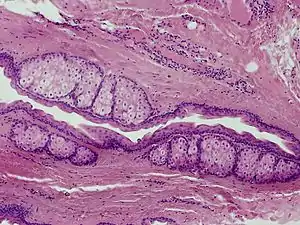

Steatocystoma multiplex

Steatocystomas are thought to come from an abnormal lining of the passageway to the oil glands (sebaceous duct).